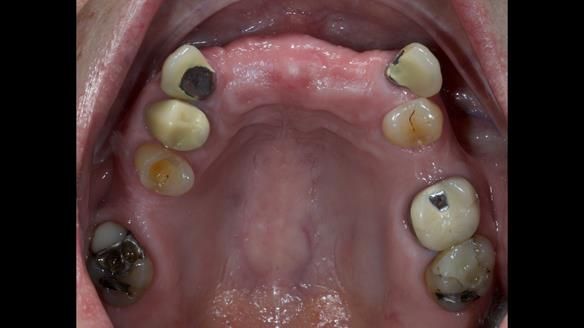

This is one of those cases that reminds me why I love removable prosthodontics. Pam was an absolute joy to treat — we were on the same page throughout. Her old upper flexible denture was loose, uncomfortable, and unaesthetic. We replaced it with a carefully designed metal-based upper partial denture/splint and new porcelain-bonded-to-zirconia (PBZ) crowns for the canines. The result is stable, comfortable, and natural-looking.

- Diagnosis and plan – Flexible upper denture ill-fitting with poor stability, retention, and appearance. Plan: metal-based upper partial denture/splint with lighter porcelain-bonded-to-zirconia crowns on UR3 and UL3.

- PBZ crowns provided – prepare, temporise, and make impressions for zirconia-bonded crowns (UR3, UL3).

- Metalwork framework try-in – to verify fit, path of insertion, and support.